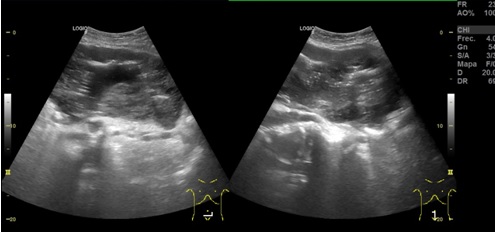

Hallazgos ecográficos: en región umbilical se aprecia una neoformación de contenido heterogéneo de unos 15 cm de diámetro. Imágenes compatibles con Esteatosis hepática. Quistes renales derechos. Esplenomegali.